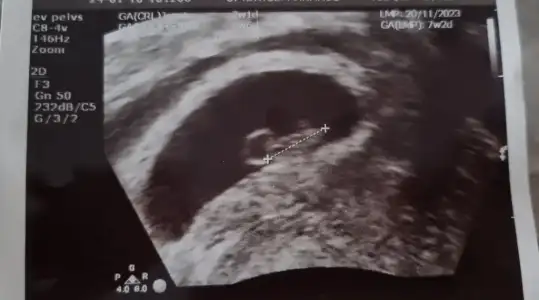

arkadaslar merhabaalar yasayan varsa bi yardimci olabilirmisiniz 9 aralikta 5. gun embiriyosu transferi oldum taze transfer suan 7+4 teyiz 5+4te yolku gorduk bebisi ve kalbi duyucaktik carsamba gunu 7+2 ken ama sali gunu gece ani bi kanamayla hastaneye gittik adet kanamasi gibi ama temiz kan renginde yogun bi kanamam oldu ve hem kucuk hemde asiri buyuk el kadar ve avuc ici kadarda degisen kocaman cigere benzer pihtilar geldi ama agri sizi yoktu kalp atisini duydum gelisiminede iyi dedi ama kanama alanim cok buyukmus gorsel ekliyorum ben yumurta toplamadan beri progestan 200 luk fitil seklinde gunde 3 tane aliyodum simdi progestan dex ekledi gunde 1 kere seklinde benim gibi durum yasayip gecen var mi kalbim sıkışıyo o kadar kahroldum ki olumlu dusunemez oldum 😢

altinda falan diye bi ibare yapmadi ama resim ekledim ilk resimde kesenin saginda tarali alan boyutta 4.2cm uzunlukta genislik 1.35cm doktorum dediki hastalar kanamadan korkar ama ben kanamasini severim cunku icerde basinc olusturmaz dedi kanama biraz kesildi gibi 2. gun temiz kan ara ara yine geliyodu ama bugun hep eski kan seklinde nokta gibi geldi 😢